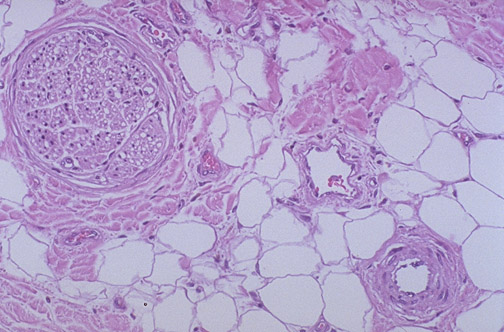

Seen here are a normal

arteriole

alongside a normal

venule

and a small

peripheral nerve

, all in cross section. The vascular supply and nerves to tissues are often grouped into a neurovascular bundle.